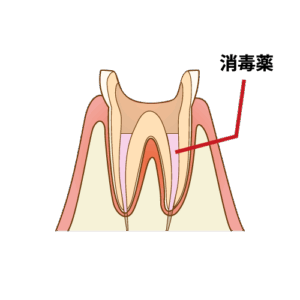

⏫④数回治療することで細菌も取り出せ、神経の部屋が段々綺麗になっていきます。

⏫⑤膿が出てこなくなれば、根管治療も終盤です。膿を取り切った後は再感染リスクを防ぐために薬を入れます。

神経を抜いた歯は細菌に感染しやすいので、ここで膿の取り残しなく、隙間なく薬を詰めます。